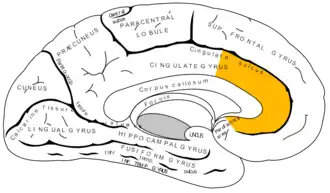

Superficie medial del hemisferio cerebral izquierdo, con el cíngulo anterior resaltado.

El córtex del cíngulo anterior (CCA) o circunvolución del cíngulo anterior es la parte frontal de la circunvolución del cíngulo, que parece un "collar" formado alrededor del cuerpo calloso, el mazo fibroso que transmite las señales neuronales entre los hemisferios cerebrales derecho e izquierdo. Consiste de las áreas de Brodmann 24, 32, y 33. Parece que juega un rol en una gama amplia de funciones autónomas, tales como regular la presión sanguínea y el ritmo cardíaco, como también para ciertas funciones cognitivas racionales, tales como la inhibición verbal, la anticipación de premio, la toma de decisiones, la empatía[1]​ y las emociones.[2][3]